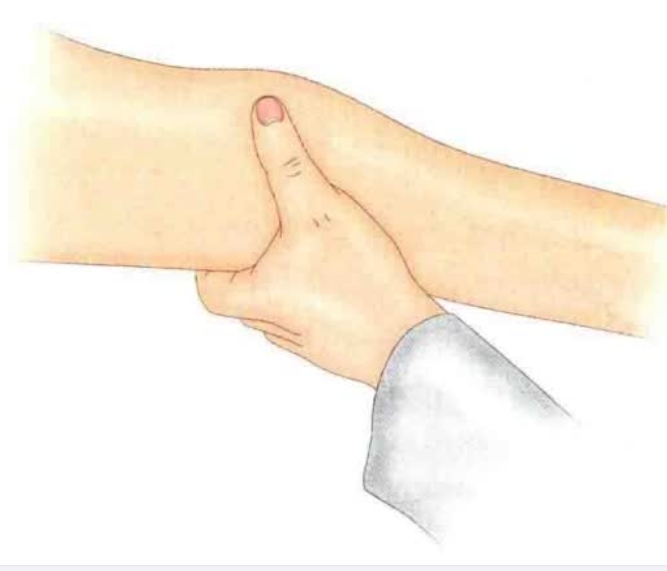

桡侧腕短伸肌起点处有压痛,压痛点位于外上髁中点远端0.5~1cm偏前处(图1)。

图1 触压痛的部位